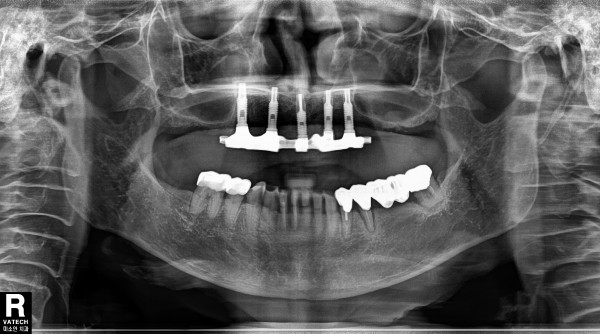

Milling bar 5 milling bar가 불편한 fixed implant bridge